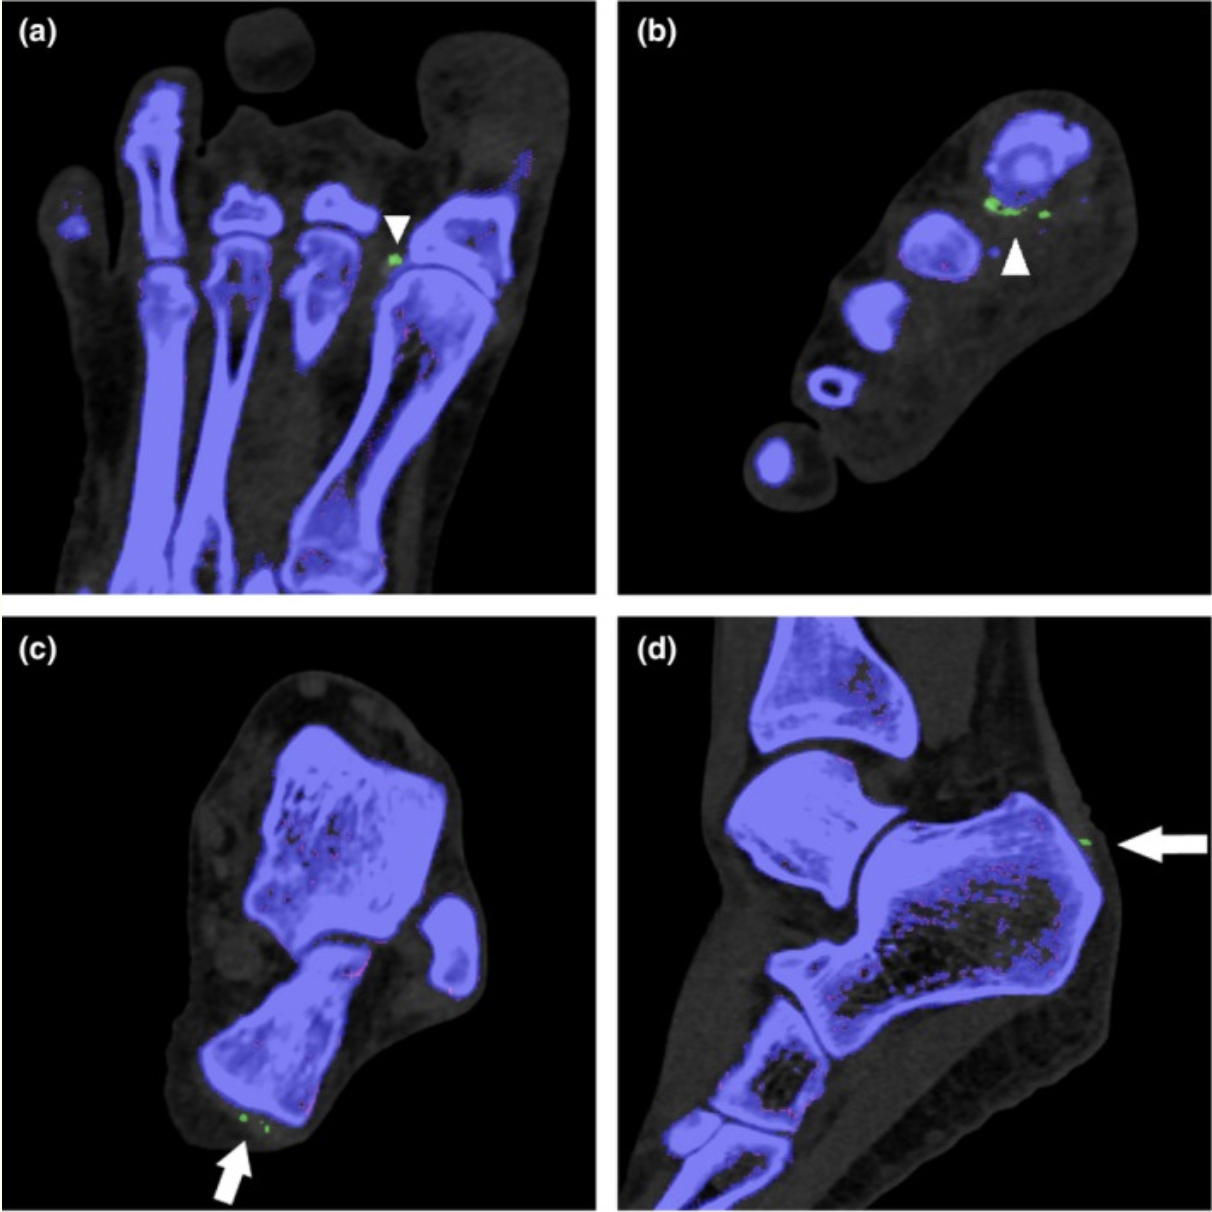

Which crystals (and related clinical condition) can DECT detect?

Monosodium urate crystals = gout